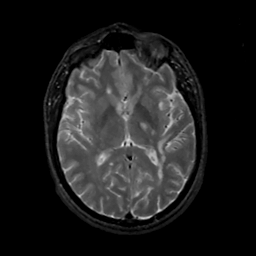

MR Study #14, June 2, 1991 -- Slice #26